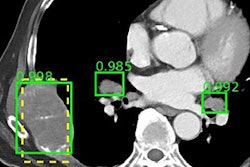

"Since most of the deep-learning algorithms that are being used today are supervised learning techniques, we'll need to provide annotations for the dataset," he said. "Usually that means drawing circles around areas of interest on the images, and it's really critical to be able to do this accurately and efficiently to build the best learning algorithms. You can't really overstate the importance of the annotations."

Commercial software is available for annotation, but there are also some open-source applications such as Horos or OsiriX that can be used, Shih said. Some researchers also utilize custom software developed using the Python or matrix laboratory (MATLAB) programming languages.